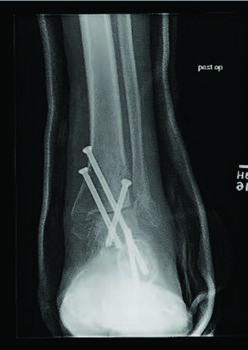

There are several studied and suggested surgical fixation options for treating complicated diabetic ankle fractures. As mentioned earlier, inappropriate treatment of these injuries can often lead to complications including the worst case scenario of Charcot arthropathy, and potential resultant limb loss. Hence, the common fundamental goals currently used for Charcot reconstruction also apply in ankle fracture fixation for patients with complicated diabetes.7 Specifically, these include obtaining a fixation construct with maximum rigidity and absolute stability, extending the fixation beyond the immediate zone of injury and planning incisions to minimize soft tissue trauma and optimize healing.4 Some fixation constructs suggested in recent literature include: circular external frame fixation; internal fixation using screws and plates; tibiotalocalcaneal (TTC) nail construct; and even locked fibular intramedullary nail fixation.4,8-10

Facaros and colleagues presented a case report of a patient with diabetes and neuropathy who sustained a displaced fibular fracture with significant joint subluxation and syndesmotic injury.11 Subsequent surgical intervention consisted of ORIF with plate fixation, multiple pro-syndesmotic screws and application of a multiplanar circular external fixator. This allowed a maximally stable and rigid construct and also allowed the patient to fully weight bear postoperatively on the external fixator. The patient underwent removal of the external fixator after 12 weeks without any long-term sequelae.11The use of multiple syndesmotic screws regardless of a syndesmotic injury is repeatedly suggested in the literature, as it allows for a more mechanically stable construct.4